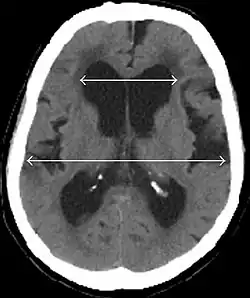

- Imaging from magnetic resonance imaging (MRI) or computed tomography (CT) is needed to demonstrate enlarged ventricles and no macroscopic obstruction to cerebrospinal fluid flow. Imaging should show an enlargement to at least one of the temporal horns of lateral ventricles, and impingement against the falx cerebri resulting in a callosal angle ≤ 90° on the coronal view, showing evidence of altered brain water content, or normal active flow (which is referred to as "flow void") at the cerebral aqueduct and fourth ventricle.

Normal pressure hydrocephalus | Brain atrophy | |

Preferable projection | Coronal plane at the level of the posterior commissure of the brain. | |

Modality in this example | CT | MRI |

CSF spaces over the convexity near the vertex (red ellipse ![]() |

Narrowed convexity ("tight convexity") as well as medial cisterns | Widened vertex (red arrow) and medial cisterns (green arrow) |

Callosal angle (blue V) | Acute angle | Obtuse angle |

Most likely cause of leucoaraiosis (periventricular signal alterations, blue arrows ![]() |

Transependymal cerebrospinal fluid diapedesis | Vascular encephalopathy, in this case suggested by unilateral occurrence |

MRI scans are the preferred imaging. The distinction between normal and enlarged ventricular size by cerebral atrophy is difficult to ascertain. Up to 80% of cases are unrecognized and untreated due to difficulty of diagnosis.[22] Imaging should also reveal the absence of any cerebral mass lesions or any signs of obstructions. Although all patients with NPH have enlarged ventricles, not all elderly patients with enlarged ventricles have primary NPH. Cerebral atrophy can cause enlarged ventricles, as well, and is referred to as hydrocephalus ex vacuo. For these reasons it's utmost important to note that Evan's index although commonly used in imaging is not very specific for NPH. One recent systematic review and meta-analysis suggests that callosal angle has high diagnostic performance and is commonly used together with Evan's index.[23]